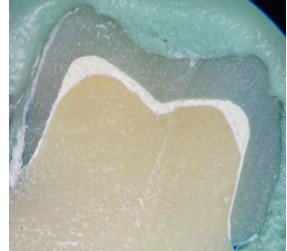

then immersed in 2% methylene blue solution for 24 h, buccolingually sectioned using a low-speed diamond disc,

and examined under a stereomicroscope (Cambridge, UK) at 30× magnification. A total of 12 specimens were

evaluated, with four distinct areas examined in each specimen (Buccal A, Buccal B, Lingual A, Lingual B), and a

total of 48 areas were assessed for microleakage. Dye penetration was scored from 0 to 4 (0 = no penetration;